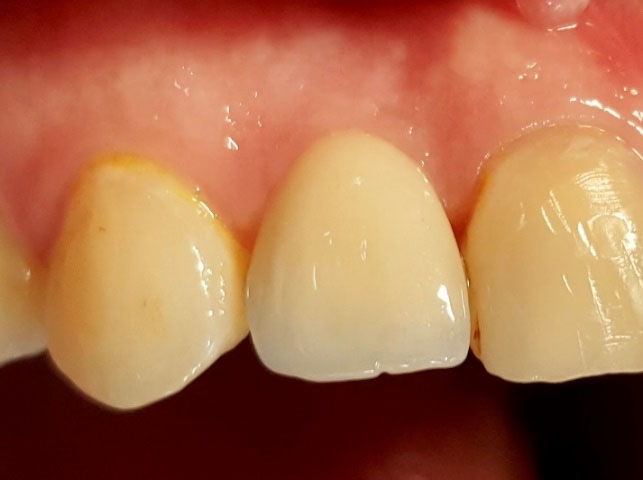

The patients were recalled for the evaluation of treatment results after two weeks, and provisional restorations were replaced with fixed restorations afterward. The patient’s PES parameters were measured by the same examiner in 6-month and 12-month follow-up recalls (Figure 2), with the 6-month interval before fixed restoration delivery and the 6-month interval after fixed restoration delivery.

Figure 2.

Fixed restoration and gingival soft tissue evaluation at 12-month follow-up recall (the same patient).